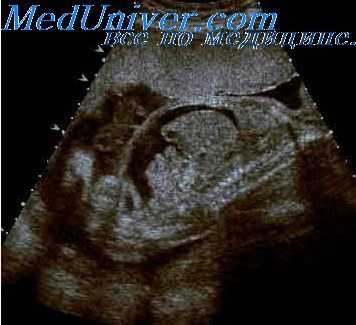

Воротниковое пространство – это скопление жидкости в области шеи плода. В нашей стране воротниковое пространство у плода исследуют в первом триместре беременности при скрининговом ультразвуковом обследовании в 10-14 недель беременности. Толщина воротникового пространства (ТВП) это область между внутренней поверхностью кожи плода и наружной поверхностью мягких тканей, покрывающих шейный отдел позвоночника.

Толщина воротникового пространства (ТВП)

Изображение воротникового пространства можно оценивать как с помощью трансабдоминального, так и трансвагинального сканирования. Оценка ТВП у плода проводится при значениях копчико-теменного размера (КТР плода) от 45 до 84 мм и позволяет заподозрить хромосомные аномалии, особенно трисомию 21-й хромосомы (синдром Дауна) и сформировать среди беременных группу риска по рождению детей с врожденной и наследственной патологией.

Толщина воротникового пространства (ТВП) на УЗИ